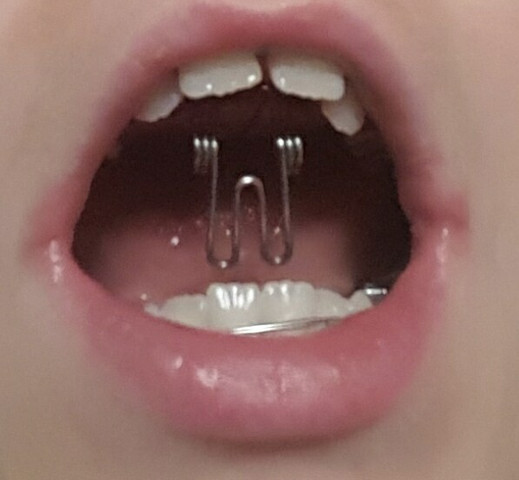

Schlangenformiges Metall In Spange Liegt Im Schliessbereich Meines

Schrauben Im Mund Wieso Braucht Man Das Fur Eine Zahnspange